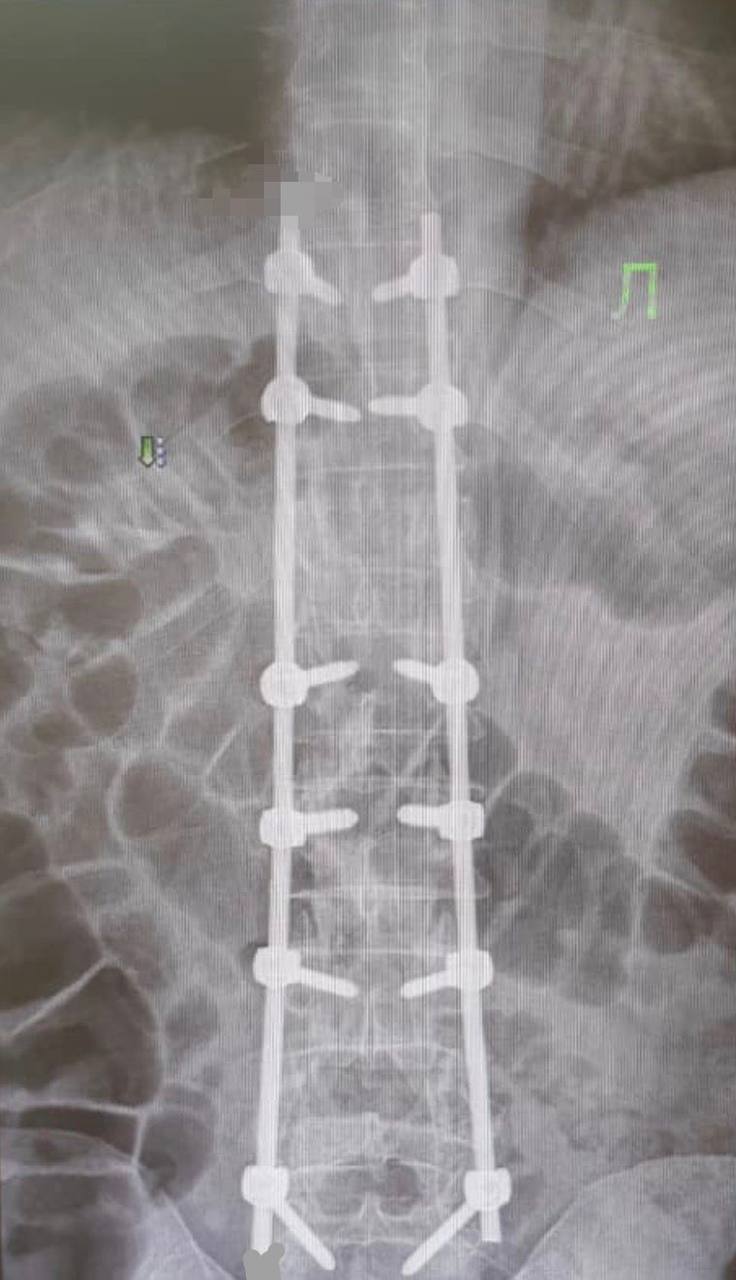

У пациента была очень тяжелая травма: компрессионно-оскольчатый перелом грудного и поясничного позвонков. В таком случае хребет разрушается из-за сильной нагрузки. Кости могут сдавить спинной мозг и нервные корешки.

Нейрохирурги провели ювелирную и невероятно сложную работу, при которой из-за одного неверного движения мужчина навсегда остался бы прикован к коляске. К счастью, операция прошла успешно. Уже на второй день пациент начал сам вставать с кровати и даже ходить по палате, рассказали в Минздраве Ингушетии.